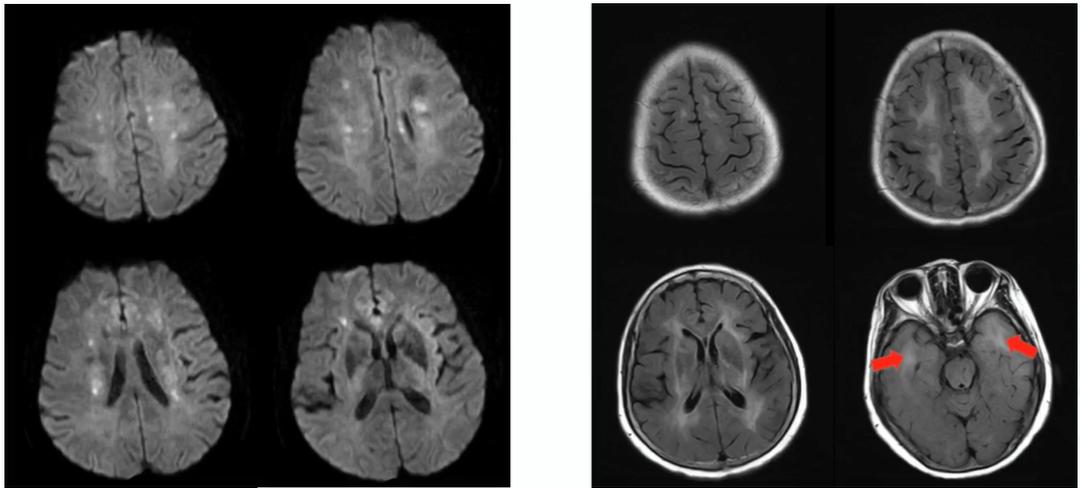

除了DWI显示的双侧半球分水岭急性梗死,FLAIR发现多发脑白质高信号,累及双侧颞极。

1. 白质高信号,特征部位包括颞极、额极、外囊,如图蓝箭所指。

2. 腔隙,如图绿箭所指。

3. 微出血(MB),如图红箭所指。

4. 脑萎缩,如图白箭所指。